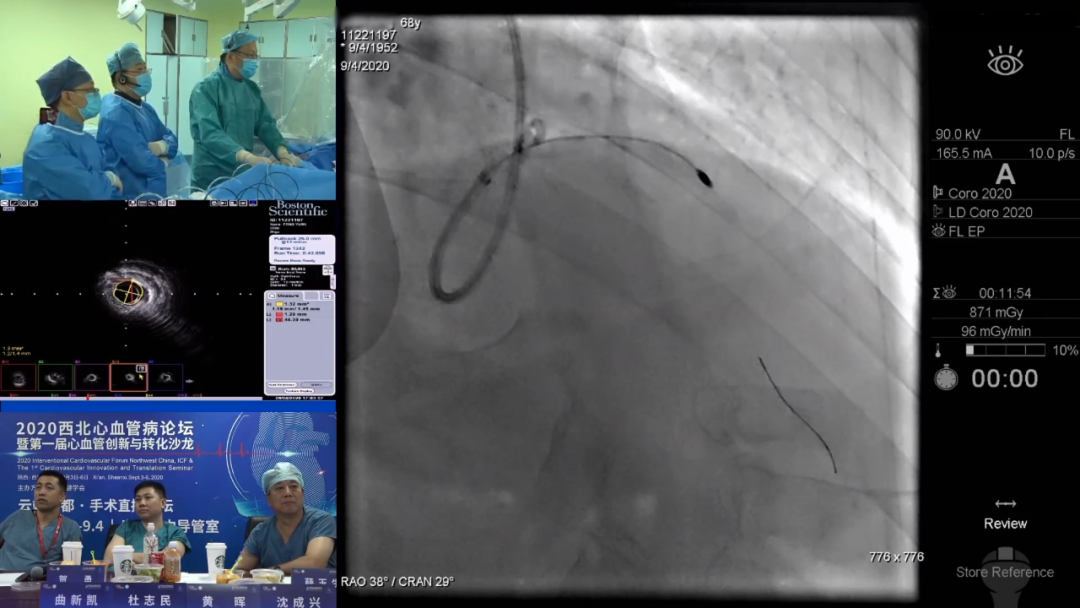

温尚煜教授演示的手术中,患者是一位68岁男性,3周前患者因胸闷胸痛就诊,冠脉造影提示前降支重度狭窄,近中段严重迂曲伴严重钙化,IVUS图像显示血管内360度环形钙化。贺勇教授观看演示时指出该患者钙化严重,同时存在严重成角,病情极其复杂,如果单用球囊可能无法打开病变,建议主动旋磨,同时注意不要旋磨至中段扭曲成角处。温尚煜教授最终应用旋磨技术,分段控制性旋磨前降支近端,并联合棘突球囊成功打开病变,顺利植入支架。